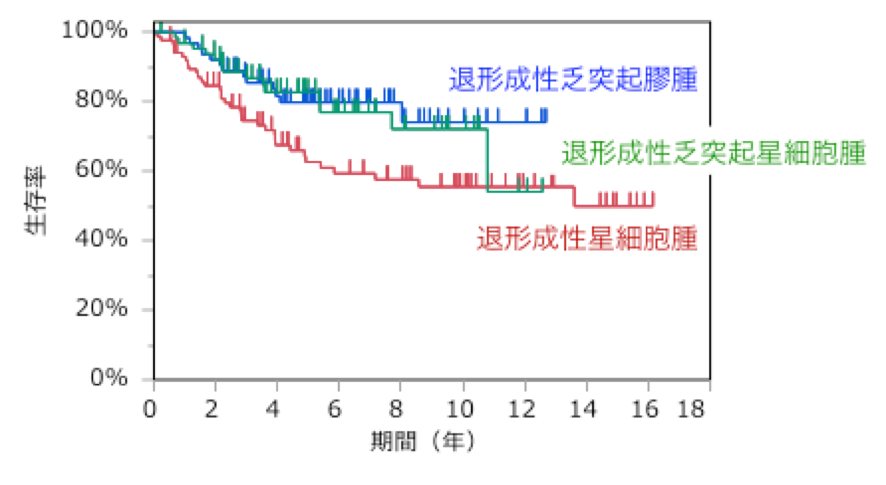

平均余命と生存率

希突起膠腫のある人の生存率は、他のほとんどの脳腫瘍よりも高くなります。利用可能な治療選択肢は数多くあり、希突起膠腫は治療によく反応するようです。この病気を完全に取り除くことができるのは異例ですが、希突起膠腫のある人の寿命を延ばすことは十分に可能です。

希突起膠腫のある人の平均余命は、腫瘍の悪性度および診断の早さによって異なります。人それぞれの状況は異なり、平均余命の統計には全体的な健康状態やケアの質などの個別の要因が考慮されていないことを覚えておくことが重要です。

一般に、グレード II 希突起膠腫の患者は、診断後約 12 年間生存する可能性があります。グレード III 希突起膠腫の患者の余命は平均 3.5 年と予想されます。

今後の見通しと再発

希突起膠腫腫瘍の見通しは、腫瘍のグレード、診断される人の全体的な健康状態、および腫瘍がどのくらい早期に診断されたかによって異なります。早期に診断され治療を開始した人は生存の可能性が高くなります。

他のすべての神経膠腫と同様、希突起膠腫は再発率が非常に高く、時間の経過とともに徐々に悪性度が増加することがよくあります。再発腫瘍は、より強力な化学療法や放射線療法で治療されることがよくあります。